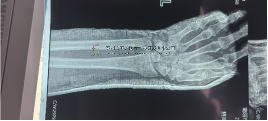

本病例由中國中醫(yī)科學(xué)院望京醫(yī)院骨創(chuàng)傷一科提供

【基本資料】患者,男,42歲

術(shù)前X片